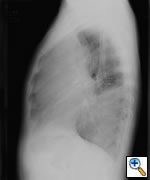

Any anterior mediastinal mass (Figures 1, 2) must be considered suspect for germ cell tumor, especially in a young male. Errors in diagnosis are not uncommon and can result in mismanagement of a potentially curable patient. All patients with an anterior mediastinal mass should have alpha-fetoprotein (AFP), β-human chorionic gonadotropin (β-HCG), and lactate dehydrogenase (LDH) levels drawn at the outset. The different types of germ cell histologies are shown in Figure 3.